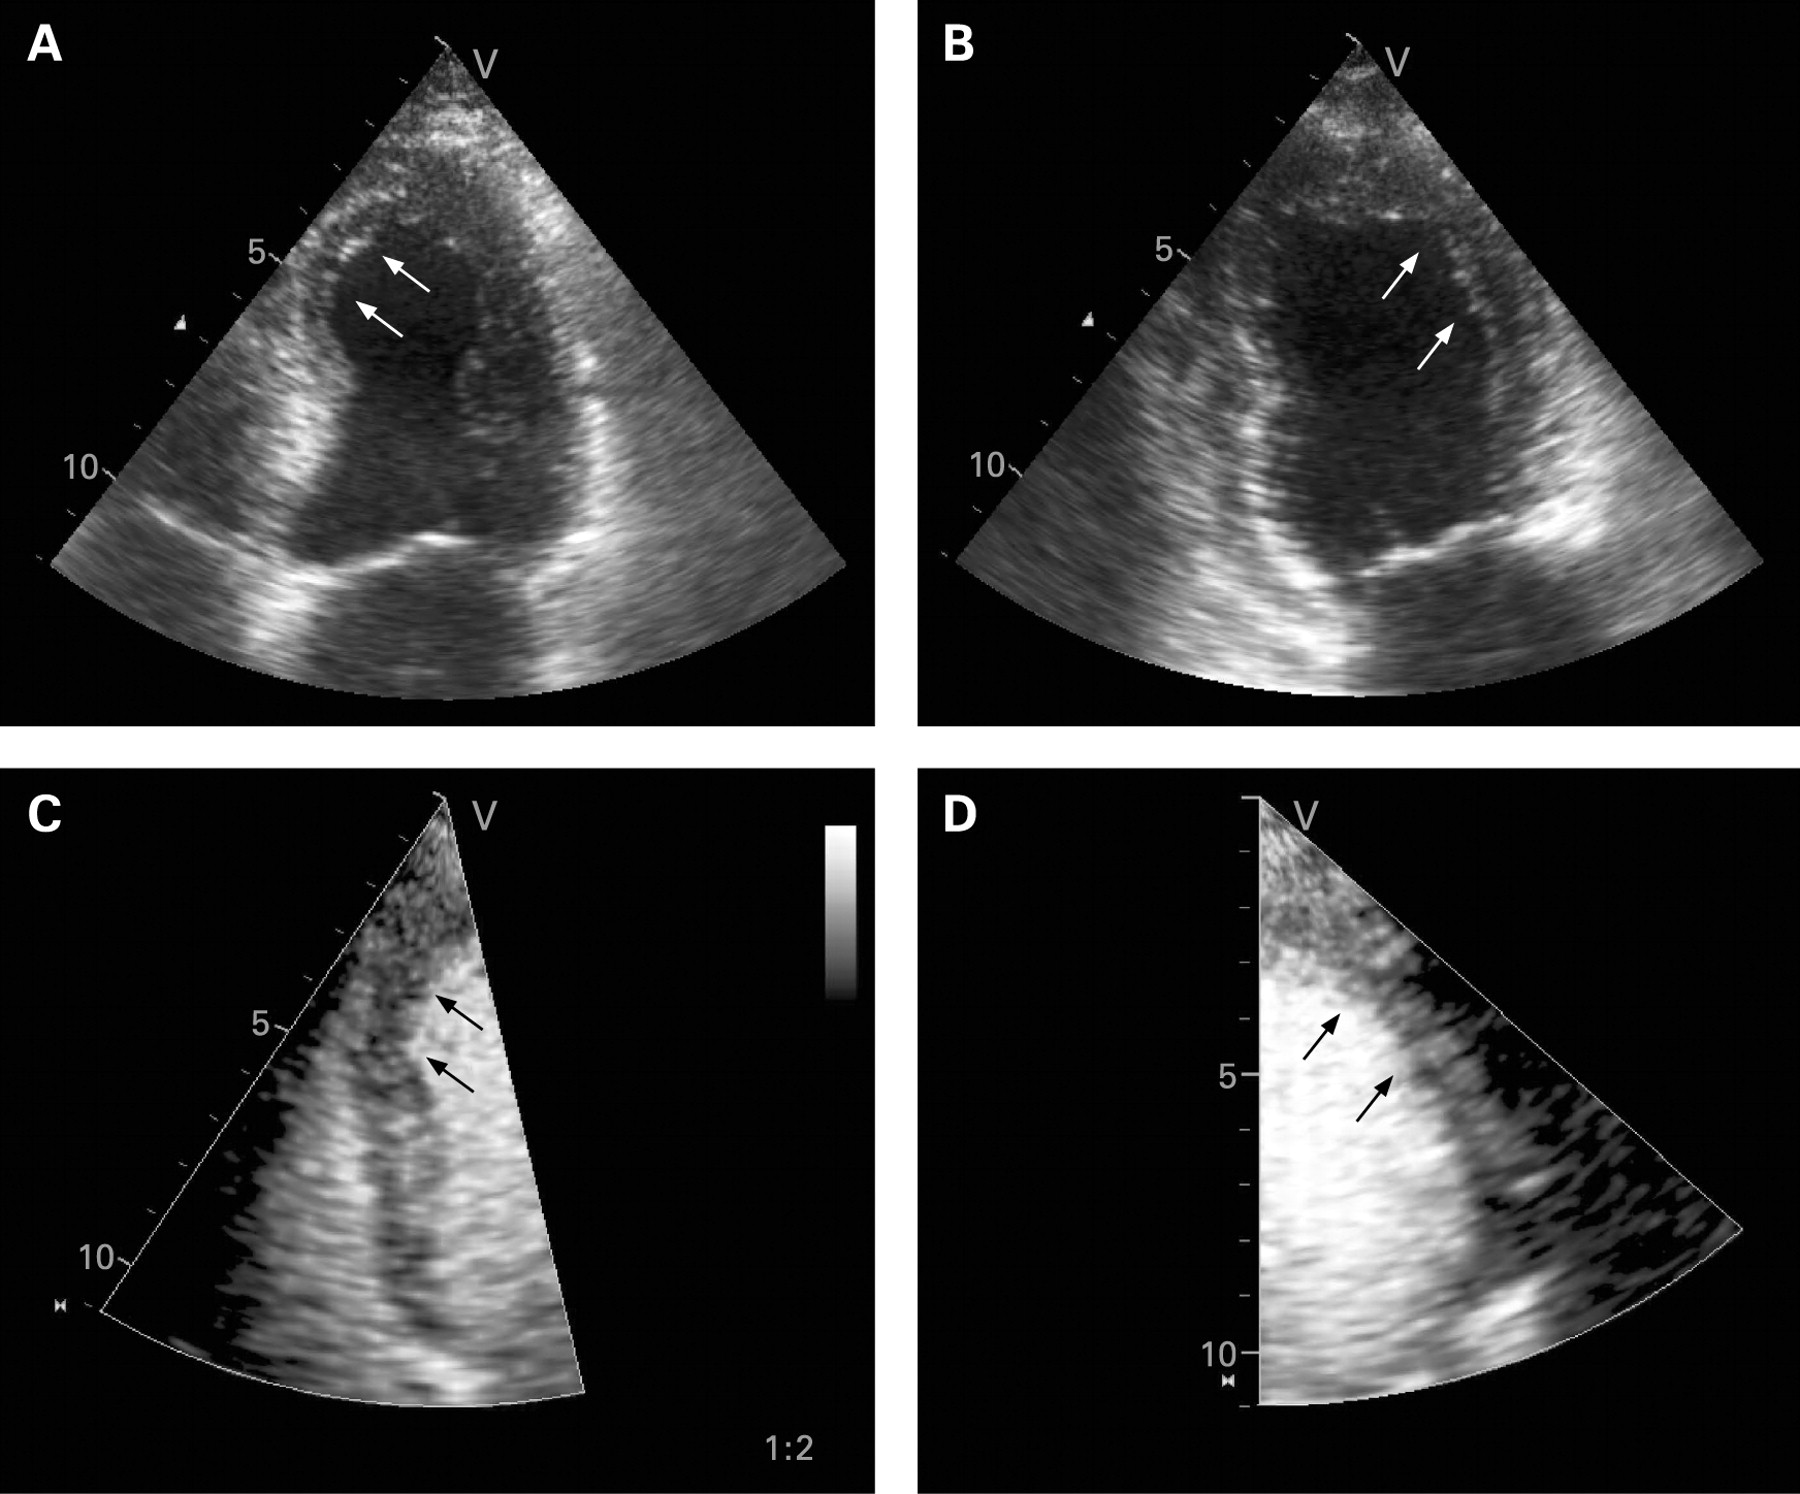

Эхокардиография является полезной методикой для стратификации риска и оценки прогноза после острого инфаркта миокарда. Показано, что для получения прогностической информации можно использовать множество традиционных эхокардиографических параметров, таких как объёмы и фракция выброса левого желудочка, индекс движения стенки, объём левого предсердия и наличие митральной регургитации. Разработка методов тканевой допплерографии и “speckle tracking” привела к появлению новых прогностических параметров, таких как деформация, скорость деформации и диссинхрония левого желудочка. Методика контрастной эхокардиографии позволяет оценивать перфузию миокарда и целостность микрососудистого кровоснабжения, предоставляет ценную информацию о жизнеспособности миокарда, тесно связанной с прогнозом. Стресс-эхокардиография позволяет выявить ишемию и жизнеспособный миокард, допплерография коронарных артерий — оценить резерв коронарного кровотока, и, наконец, трёхмерная эхокардиография даёт оптимальную информацию об объёмах, функции и сферичности левого желудочка, которые также являются важными параметрами долгосрочного прогноза.